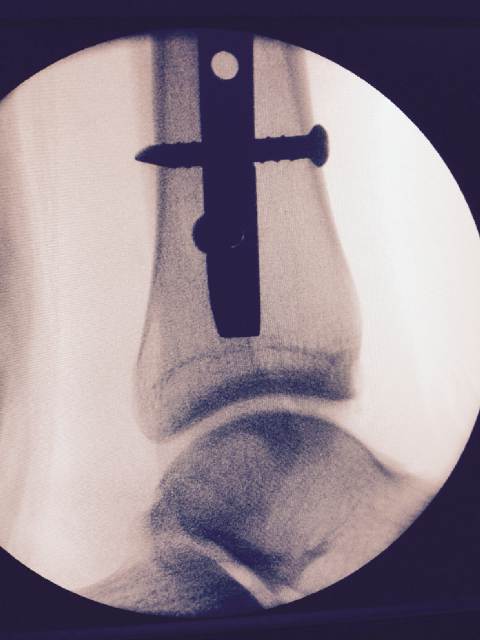

La fractura de Sebastián Crismanich fue una de las noticias negativas para el deporte argentino durante la última semana. En un combate durante el Abierto de México, el correntino se quebró la tibia y también se rompió el peroné, todo por una maniobra ilegal de un rival trinitense. El campeón olímpico en Londres 2012 tuvo que pasar por el quirófano para reparar la pierna dañada. La recuperación demandará seis meses como mínimo, con lo que quedará afuera de los Panamericanos de Toronto 2015 y se pondrá como nuevo objetivo los Juegos de Río 2016.

Ya de regreso en su provincia, luego de la intervención en Capital, el taekwondista planificó sus trabajos de rehabilitación y mostró en una placa el clavo endomedular en su pierna. Dentro de un tiempo va a quedar como un recuerdoâ?¦ Gabriel Taraburelli, el entrenador nacional, habló sobre la lesión y contó su optimismo: â??Es un luchador de la vida. Pelea frente a las dificultades. Va a ser un obstáculo más para seguir adelante. Ya puso su foco en las próximas metasâ??.